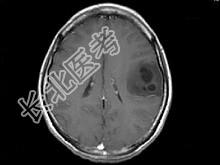

- 单项选择题女,33岁, 3个月前有右上肢及右颜面部麻木,伴耳鸣及头昏, 根据所提供图像,最可能的诊断是 ( )

A、脑脓肿

B、星形细胞瘤

C、脑结核

D、脑转移瘤

E、脑血吸虫病